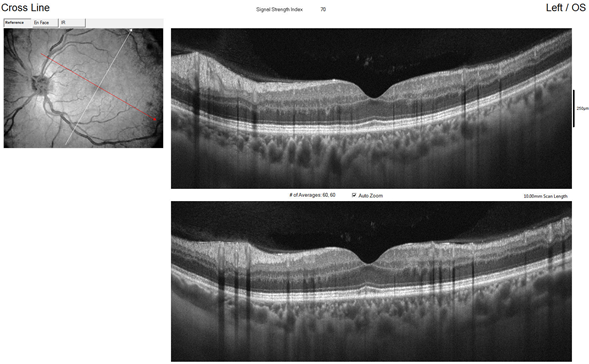

Fundus photography confirmed the macular findings, and AF showed hypoautofluorescent lesions over the optic nerve and macula (Figure 1). Computerized perimetry revealed a non-specific defect in OD and a centrocecal defect in OS (Figure 2). OCT of the optic nerve showed mild superior elevation in OS with RNFL analysis (Figure 3), and marked vascular density reduction in 360° in the optic nerve of OS (Figure 4). Macular OCT revealed an alteration in the external plexiform layer of OS with abundant temporal hyperreflective lesions, and a preserved foveal architecture in both eyes (Figure 5). OCTA of the macula showed a decrease in vascular density in the deep superior and choriocapillaris layers (Figure 6). Based on these findings, aspirin was reintroduced, and a follow-up was scheduled in 4 weeks with computerized perimetry, OCT, and OCTA, with a presumptive diagnosis of NAION and PAMM.

Figure 5 Preserved foveal architecture in both eyes.

Figure 6 OCTA of the macula showed a decrease in vascular density in the deep superior and choriocapillaris layers.

At the follow-up, the patient reported that despite persistent visual symptoms, these did not significantly affect his visual field. Ophthalmic exams showed improvement in the visual field, with a more limited paracentral scotoma (Figure 7). Macular OCT showed fewer hyperreflective lesions in the temporal external plexiform layer, but worsening RNFL analysis due to increased optic nerve edema in OS secondary to NAION (Figure 8). OCTA indicated improved vascular perfusion in all retinal layers (Figure 9).

Figure 9 OCTA indicated improved vascular perfusion in all retinal layers.